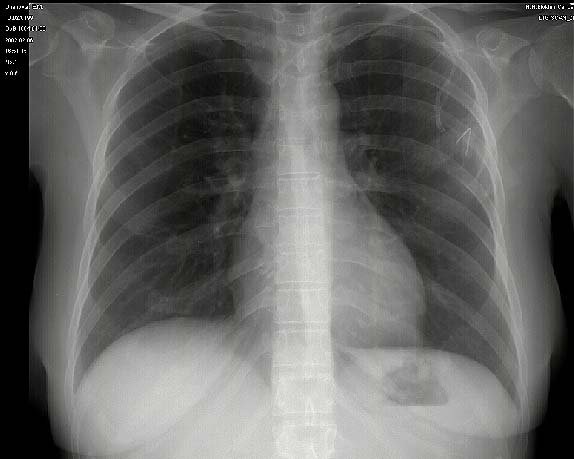

Pracownia Rentgenodiagnostyki w Tczewie zaprasza mieszkańców miasta na bezpłatne badania radiologiczne klatek piersiowych (duże zdjęcie rtg płuc) w ramach zorganizowanego przez Urząd Miejski w Tczewie programu profilaktycznego na 2010 roku.

Dodajmy, że to nie pierwsza tego typu akcja w naszym mieście. W ubiegłym roku ponad 6 tysięcy mieszkańców grodu Sambora skorzystało z profilaktycznych badań rentgenowskich. Dzięki nim wykryto 8 świeżych zmian gruźliczych, 12 zmian pogruźliczych, 31 zmian typu - guz płuca oraz zmiany meta, 44 zmiany pneumoniczne (zapalne) i 66 zmian o charakterze łagodnym w płucach. Badania pozwoliły również na znalezienie 208 zmian w układzie sercowo-naczyniowym, w tym powiększeń sylwetki serca oraz wad serca. Ponadto stwierdzono 79 zmian kostnych, w tym 2 skoliozy kręgosłupa piersiowo-lędźwiowego.